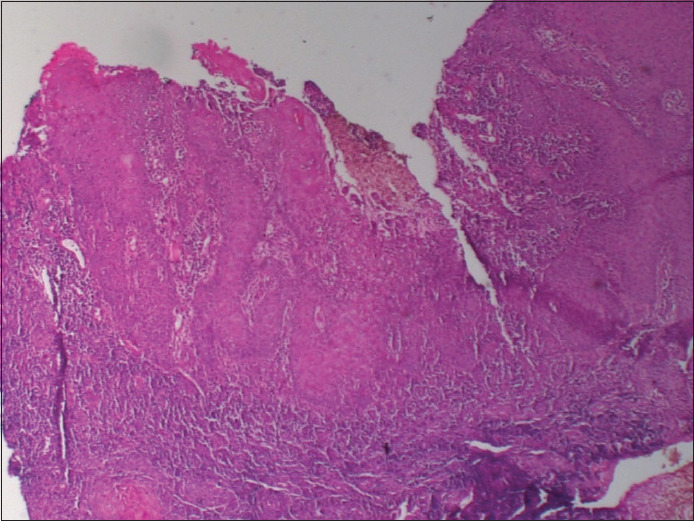

Donovanosis is a chronic granulomatous ulcerative sexually transmitted infection caused by Klebsiella (Calymmatobacterium) granulomatis. A 39-year-old female patient with underlying HIV infection presented to the department of dermatology outpatient department with a painless ulcer over the left labia majora for 3 months. Histopathological examination revealed histiocyte which contains granular material resembling coccobacilli and Giemsa staining was positive for Donovan bodies. She was treated with doxycycline 100 mg twice daily and azithromycin 1 g once weekly for 3 weeks and further azithromycin 1 g weekly for the next 9 weeks till complete healing of the lesion. Due to the rarity of this condition in our region, we present this case of donovanosis in an HIV-positive female patient.